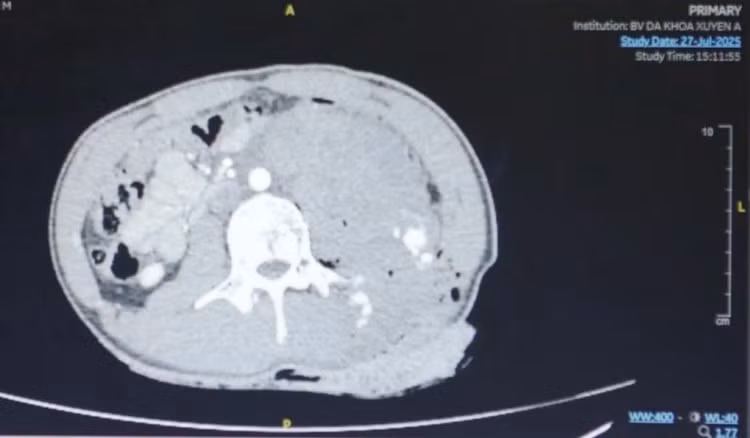

Ngay khi tiếp nhận, các bác sĩ Khoa Cấp Cứu đã nhanh chóng cầm máu và hồi sức cho huyết động học ổn định rồi tiến hành chụp MSCT chẩn đoán. Kết quả ghi nhận có một vết thương vùng hông lưng kéo dài 15cm, bị dao đâm xuyên thấu bụng, có hơi tự do ổ bụng.

hinh-anh-ct-vet-thuong-vung-bung-chay-mau-768x449.jpg

Hình ảnh MSCT cho thấy vết thương bị dao đâm ở vùng bụng - Ảnh BVCC